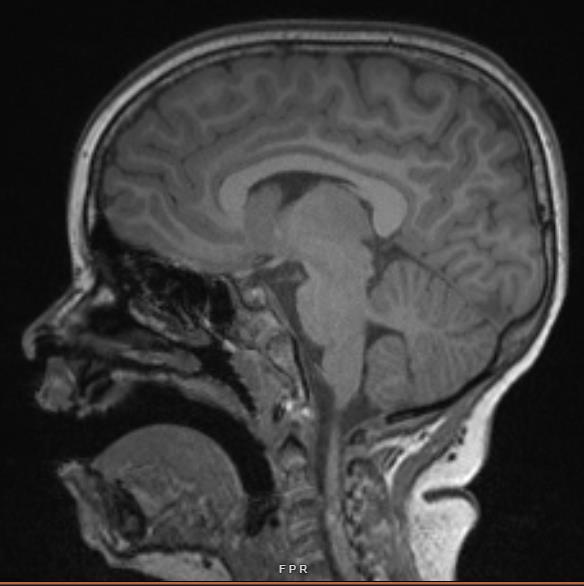

Introduction

Albright hereditary osteodystrophy (AHO) is caused by heterozygous inactivating mutations in GNAS, the gene encoding the α-subunit (Gαs) of the stimulatory G protein (Gs). Gs couples heptahelical receptors for numerous hormones and neurotransmitters to stimulate cAMP formation by adenylyl cyclase. Patients with GNAS mutations on the maternally-inherited allele have a condition termed pseudohypoparathyroidism type 1A (PHP1A) and manifest resistance to multiple Gs-coupled hormones (e.g. PTH, TSH, LH/FSH, GHRH, calcitonin) in addition to having severe obesity, short stature, brachydactyly, and subcutaneous ossifications (Fig. 1). Patients with GNAS mutations on the paternally-inherited allele have a condition termed pseudopseudohypoparathyroidism (PPHP) and have similar symptoms but do not exhibit hormone resistance or severe obesity. This genetic mechanism based on the parental mode of inheritance is called genomic imprinting. We previously developed a mouse model of AHO through targeted disruption of exon 1 of Gnas and have shown that it recapitulates the human condition in our prior investigations. Dental and craniofacial abnormalities are a significant issue in PHP1A, often leading to the need for oral surgery and orthodontic intervention. Dental abnormalities that can occur include enamel hypoplasia and opacities, deviation of root morphology, eruption disturbances, microdontia, hypodontia, and large pulp chambers (Fig. 1D). Craniofacial abnormalities also occur such as mid-face hypoplasia, craniosynostosis, and both mandibular and maxillary hypoplasia. These abnormalities lead to a large medical and financial burden for the patients. In PPHP, the extent of these dental and craniofacial abnormalities remains unclear, and our mouse model may be useful in identifying potential abnormalities. Overall, this investigation set out to investigate whether our mouse model could be utilized for further investigation of the mandibular abnormalities.

This study compared mouse correlates of PHP1A (Gnas E1+/-m) and PPHP (Gnas E1+/-p) to wild-type mice at 5 and 12 weeks of age Noticeable differences in mandibular length between mutant and wild-type mice were visually observed on radiographic high-powered jaw images. Defined measurements for assessing mandibular dimensions were then performed and analyzed via ImageJ software Although the mouse model of AHO recapitulates the condition, its use as a model for mandibular defects has not been previously determined.

Figure 1. Phenotype of Albright Hereditary Osteodystrophy. AHO is characterized by short stature (A), as well as brachydactyly (B) and brachymetacarpia/brachymetatarsia [with brachymetatarsia shown in (C)]. Dental and jaw abnormalities are also common. A panoramic radiograph of a 10-year-old subject with PHP1A (D) is shown with congenitally missing teeth including the upper left canine, 2nd molar, 2nd bicuspid, lower left 1st and 2nd bicuspids, 3rd molar, lower right 1st and 2nd bicuspids, and 3rd molar. No signs of 3rd molar development are present. The overall jaw is hypoplastic.